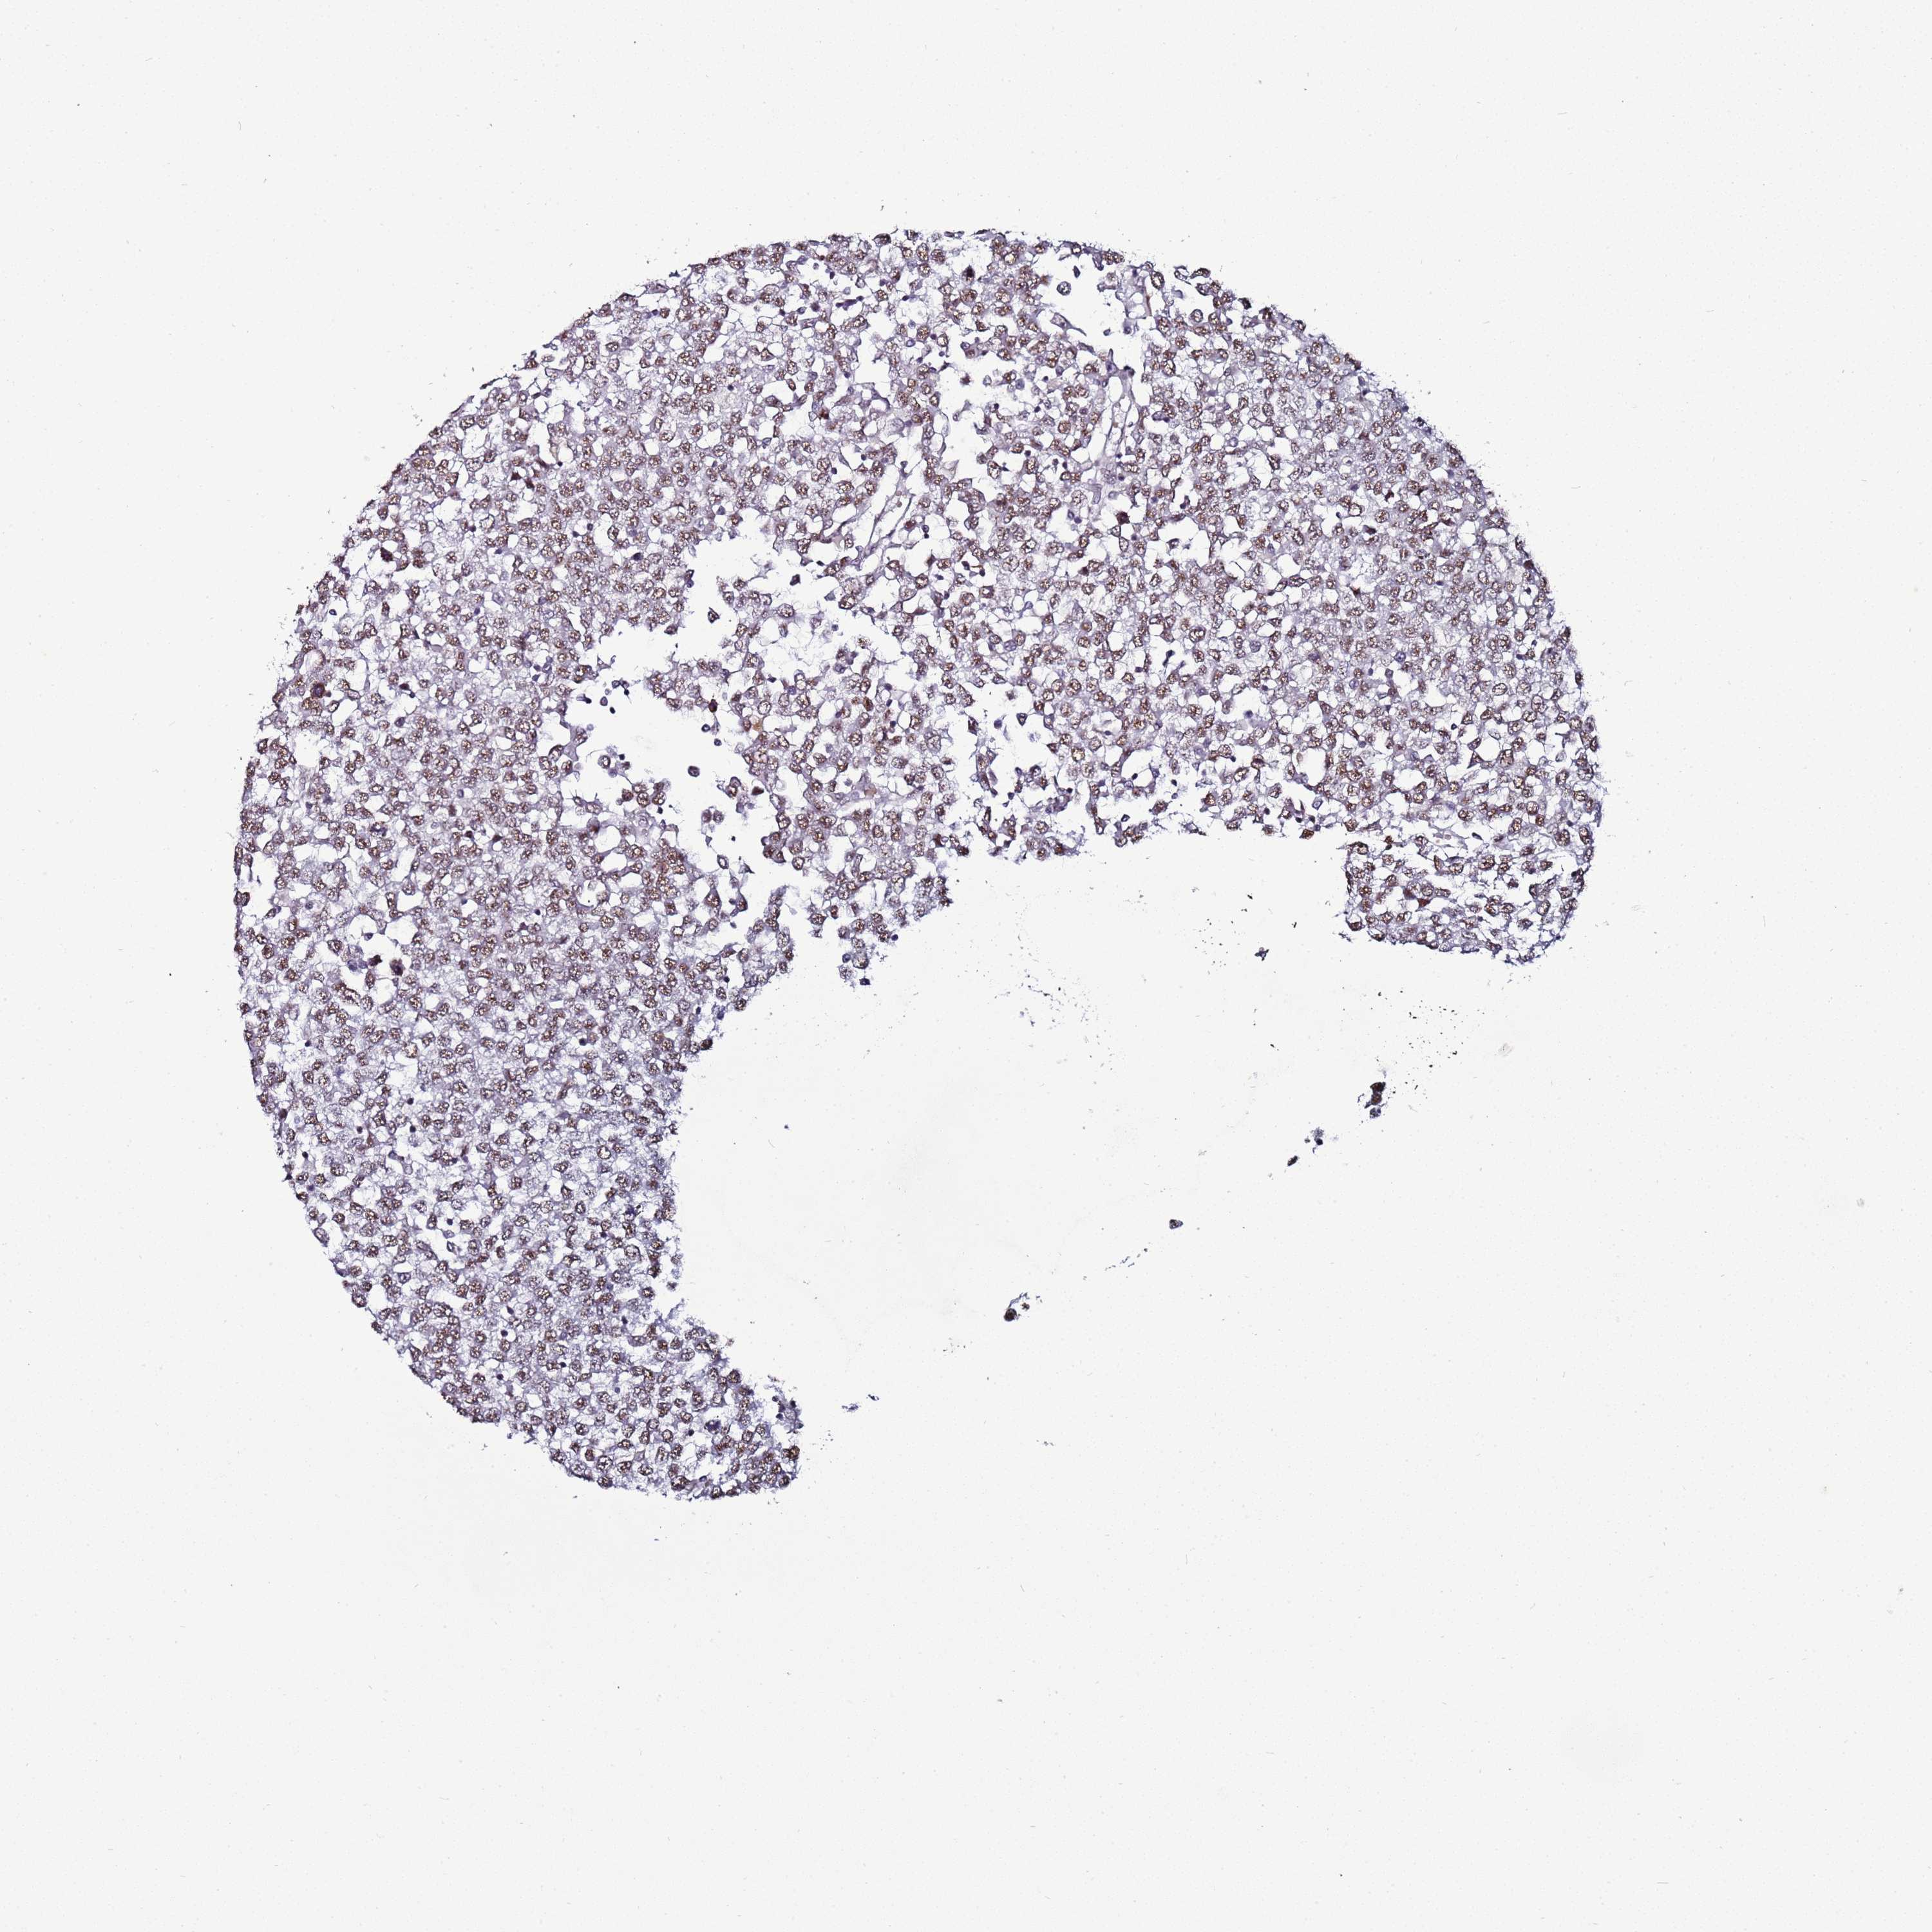

TESTIS CANCER - Protein expressioni

A mouse-over function shows sample information and annotation data. Click on an image to view it in a full screen mode. Samples can be filtered based on level of antibody staining by selecting one or several of the following categories: high, medium, low and not detected. The assay and annotation is described here.

Note that samples used for immunohistochemistry by the Human Protein Atlas do not correspond to samples in the TCGA dataset.

Antibody stainingi

Antibody staining in the annotated cell types in the current human tissue is reported as not detected, low, medium, or high, based on conventional immunohistochemistry profiling in selected tissues. This score is based on the combination of the staining intensity and fraction of stained cells.

Each image is clickable and will lead to virtual microscopy that enables deeper exploration of all samples and also displays staining intensity scores, fraction scores and subcellular localization as well as patient and tissue information for each sample.

Antibody HPA047266

Carcinoma, Embryonal, NOS

Seminoma, NOS